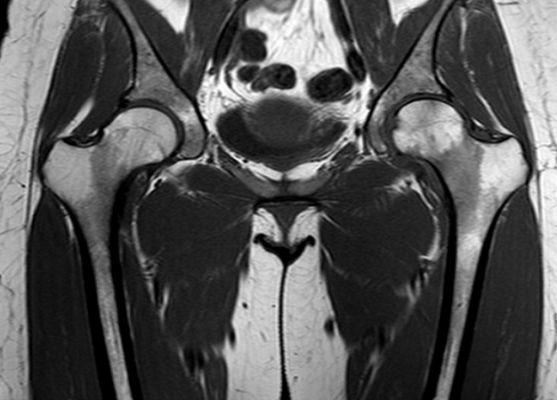

МР-скан коксофеморальных сочленений, вариант нормы

В ортопедической практике МРТ тазобедренного сустава чаще проводят для уточнения причин коксалгии - болевого синдрома в сочленении. Способ исследования не подразумевает использования ионизирующего излучения, что особенно актуально для детей и беременных женщин. Процесс создания четких снимков, которые можно увеличивать, рассматривать в объемном виде, базируется на использовании магнитного резонанса и компьютерных технологий. Для улучшения возможностей визуализации применяют контрастирование. Диагностическая ценность фото, полученных после введения гадолиния, сопоставима с результатами артроскопии - инвазивного исследования с проникновением в полость сочленения хирургических инструментов.

Интерпретацией изображений занимается врач-рентгенолог. В норме на серии томограмм травматических изменений не определяется:

структура костной ткани однородна, без дистрофических признаков;

субхондрального склероза суставных поверхностей нет;

капсула сочленений не утолщена, в полости присутствует небольшое количество синовиальной жидкости с однородным МР-сигналом;

костные крыши вертлужных впадин сформированы правильно, суставные щели равномерные, конгруэнтность (сопоставимость, согласованность) поверхностей сохранена;

целостность связочного аппарата не нарушена;

сигнал хрящевого компонента без особенностей, областей истончения нет;

краевые заострения суставных поверхностей вертлужных впадин отсутствуют;

окружающие мягкие ткани без видимой патологии;

бедренные и тазовые кости в зоне сканирования без очаговых изменений.